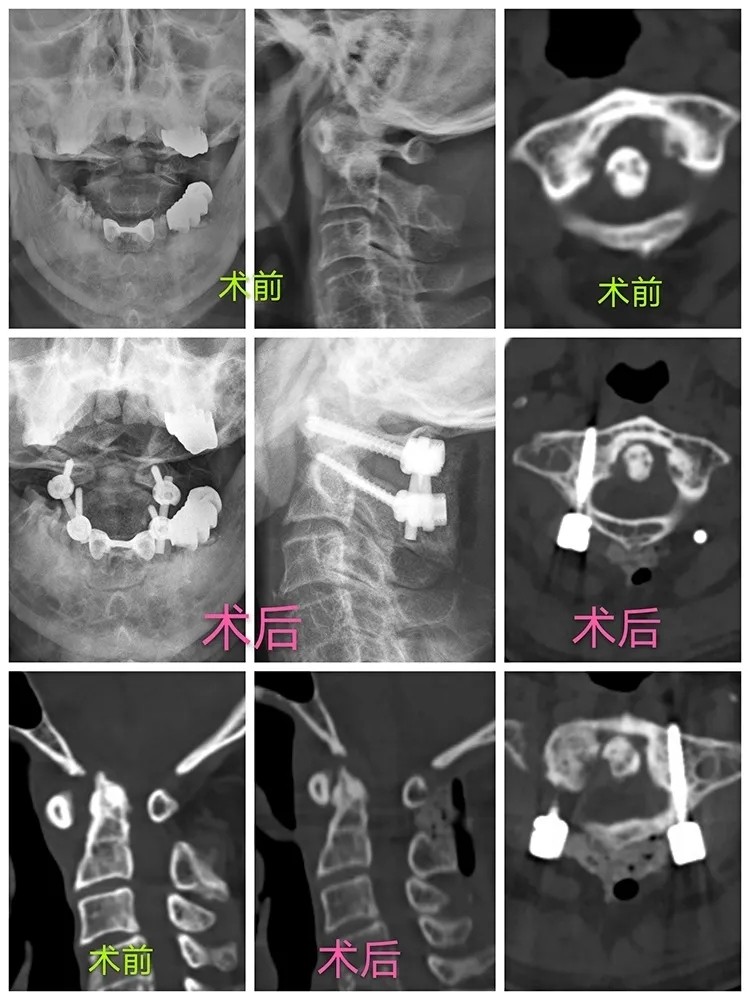

After taking a careful consideration into his medical history, physical examination and the imaging results, Prof. Lin confirmed his diagnosis that the patient had several cervical vertebra problems, including atlantoaxial dislocation, upper cervical myelopathy and high-riding left vertebral artery, so he recommended that a surgery should be performed as soon as possible. When it came to design the operative plan, there were two factors that need to be considered. One was that the patient is already 80 years old, and the other was that he had high-riding left vertebral artery with the vertebral artery dominance, which may result in a higher risk of vascular injury if a screw is used, and may further cause serious complications such as cerebral infarction or even death after surgery. After considerable discussion, the team of Prof. Lin decided to perform the surgery by following three steps: firstly, performing gradually great weight skull traction for positioning the dislocated cervical vertebra under general anesthesia; secondly, precisely inserting the screws with the help of “Tianji” surgical robot; thirdly, decompressing under 3D microscope that enables a high-definition visualization of the process.

The surgery lasted for less than 90 minutes and the peri-operative blood loss was about 70ml. During the surgery, the screws were well distributed so that the relocation of the atlanto-axial joint, and the decompression were all fully realized. The patient's symptoms were greatly relieved and his neck pain disappeared completely after the surgery, and the patient could walk freely with the neck brace on the first day after the surgery. He said gratefully with his thumbs up to Prof. Lin, "I haven't had such a good sleep for a long time, thank you very much!"